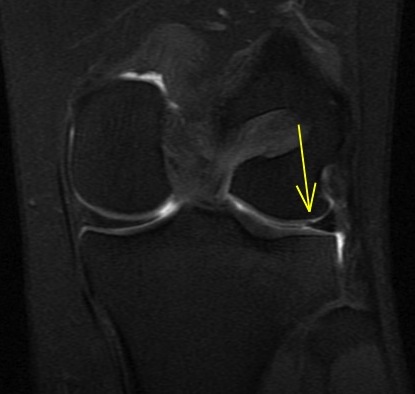

Figure 4 for case Lateral meniscus flap tear and adjacent stress fracture

Figure 4

Knee arthrogram showing lateral meniscus flap tear and adjacent stress fracture.

Lateral meniscus flap tear and adjacent stress fracture